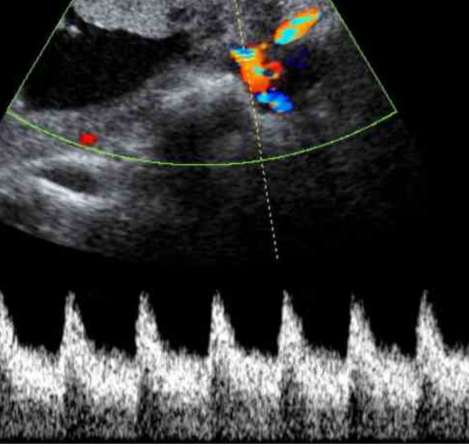

Ultrasonido Doppler Color

Un ultrasonido expone la región de interés del cuerpo a ondas sonoras de alta frecuencia. Las imágenes del ultrasonido son capturadas en tiempo real; eso es, no sólo muestran la estructura de una parte en particular del cuerpo, sino que también pueden mostrar el...